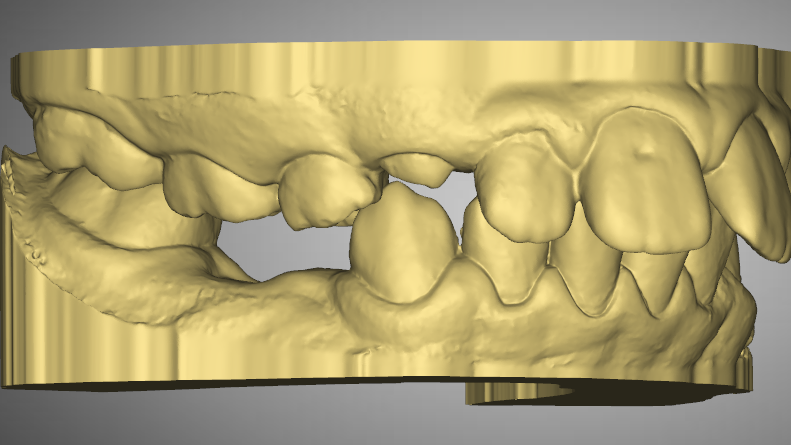

Pre-Op Analysis – 2020-11-25

- Class 2 div I and div II

- Mixed Dentition

- Yellow Stone Model = Pre-Op at 2020

- Blue Overlay = Progress scan at 2022-07-04 after about 12 months of Mybrace K1 which came after 6 months in aligners.